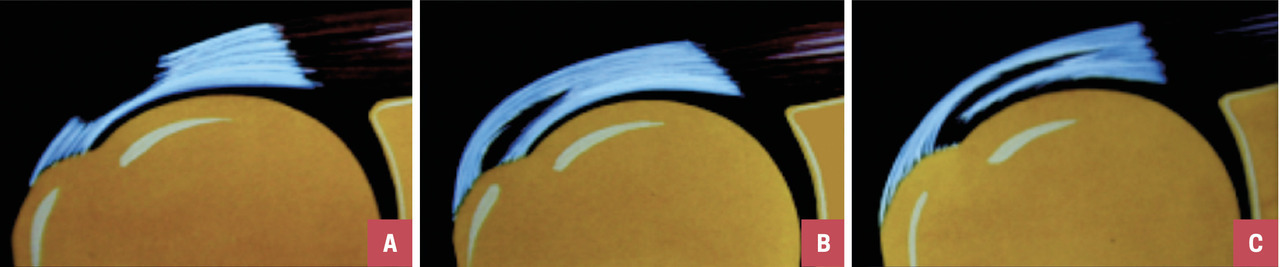

On distingue différentes lésions tendineuses  : non rompues, on parle alors de tendinopathies ; ou rompues, la rupture pouvant être partielle ou transfixiante (fig. 2 et 3).

• une rupture partielle (de tous types, fig. 2) ;

• une petite rupture transfixiante du supraépineux, non détectable au test de force manuel.